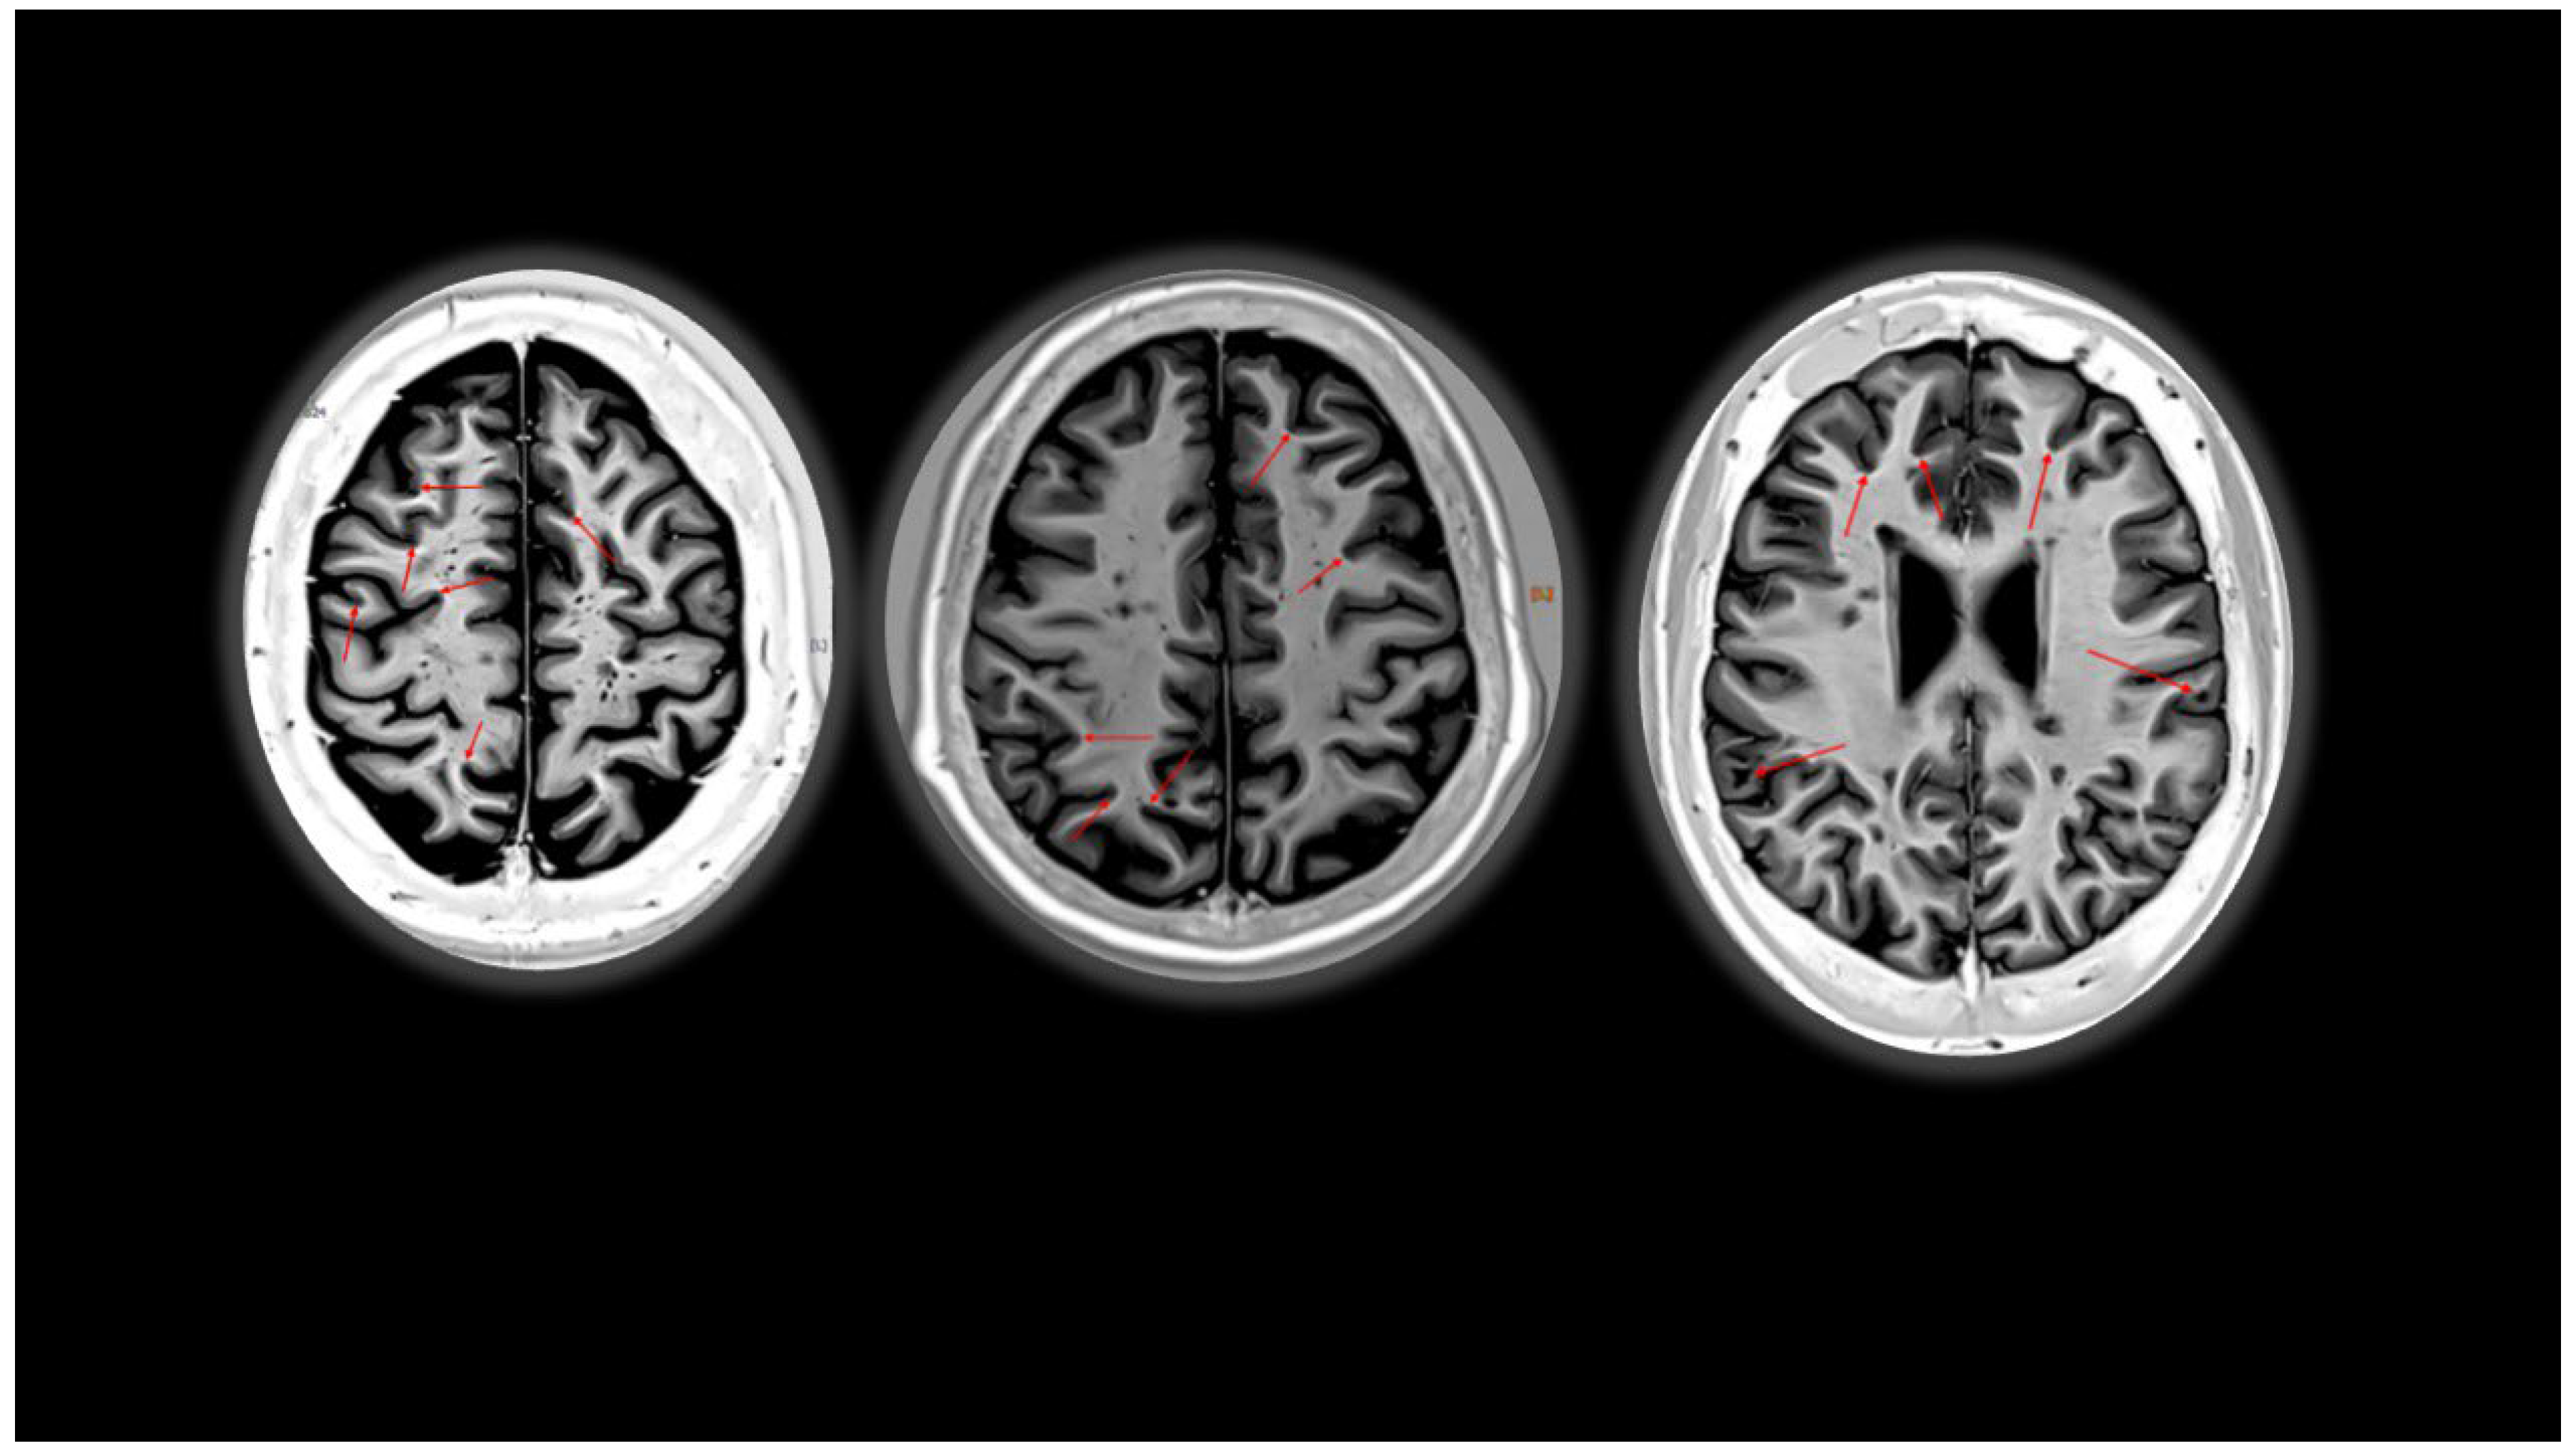

- Kocsis, K.; Szabó, N.; Tóth, E.; Király, A.; Faragó, P.; Kincses, B.; Veréb, D.; Bozsik, B.; Boross, K.; Katona, M.; et al. Two Classes of T1 Hypointense Lesions in Multiple Sclerosis with Different Clinical Relevance. Front. Neurol. 2021, 12, 619135. [Google Scholar] [CrossRef] [PubMed]

- Calvi, A.; Tur, C.; Chard, D.; Stutters, J.; Ciccarelli, O.; Cortese, R.; Battaglini, M.; Pietroboni, A.; De Riz, M.; Galimberti, D.; et al. Slowly expanding lesions relate to persisting black-holes and clinical outcomes in relapse-onset multiple sclerosis. Neuroimage Clin. 2022, 35, 103048. [Google Scholar] [CrossRef]

- Elliott, C.; Wolinsky, J.S.; Hauser, S.L.; Kappos, L.; Barkhof, F.; Bernasconi, C.; Wei, W.; Belachew, S.; Arnold, D.L. Slowly expanding/evolving lesions as a magnetic resonance imaging marker of chronic active multiple sclerosis lesions. Mult. Scler. J. 2019, 25, 1915–1925. [Google Scholar] [CrossRef] [PubMed]

- Elliott, C.; Arnold, D.; Chen, H.; Ke, C.; Zhu, L.; Chang, I.; Cahir-McFarland, E.; Fisher, E.; Zhu, B.; Gheuens, S.; et al. Patterning chronic active demyelination in slowly expanding/evolving white matter MS lesions. Am. J. Neuroradiol. 2020, 41, 1584–1591. [Google Scholar] [CrossRef]